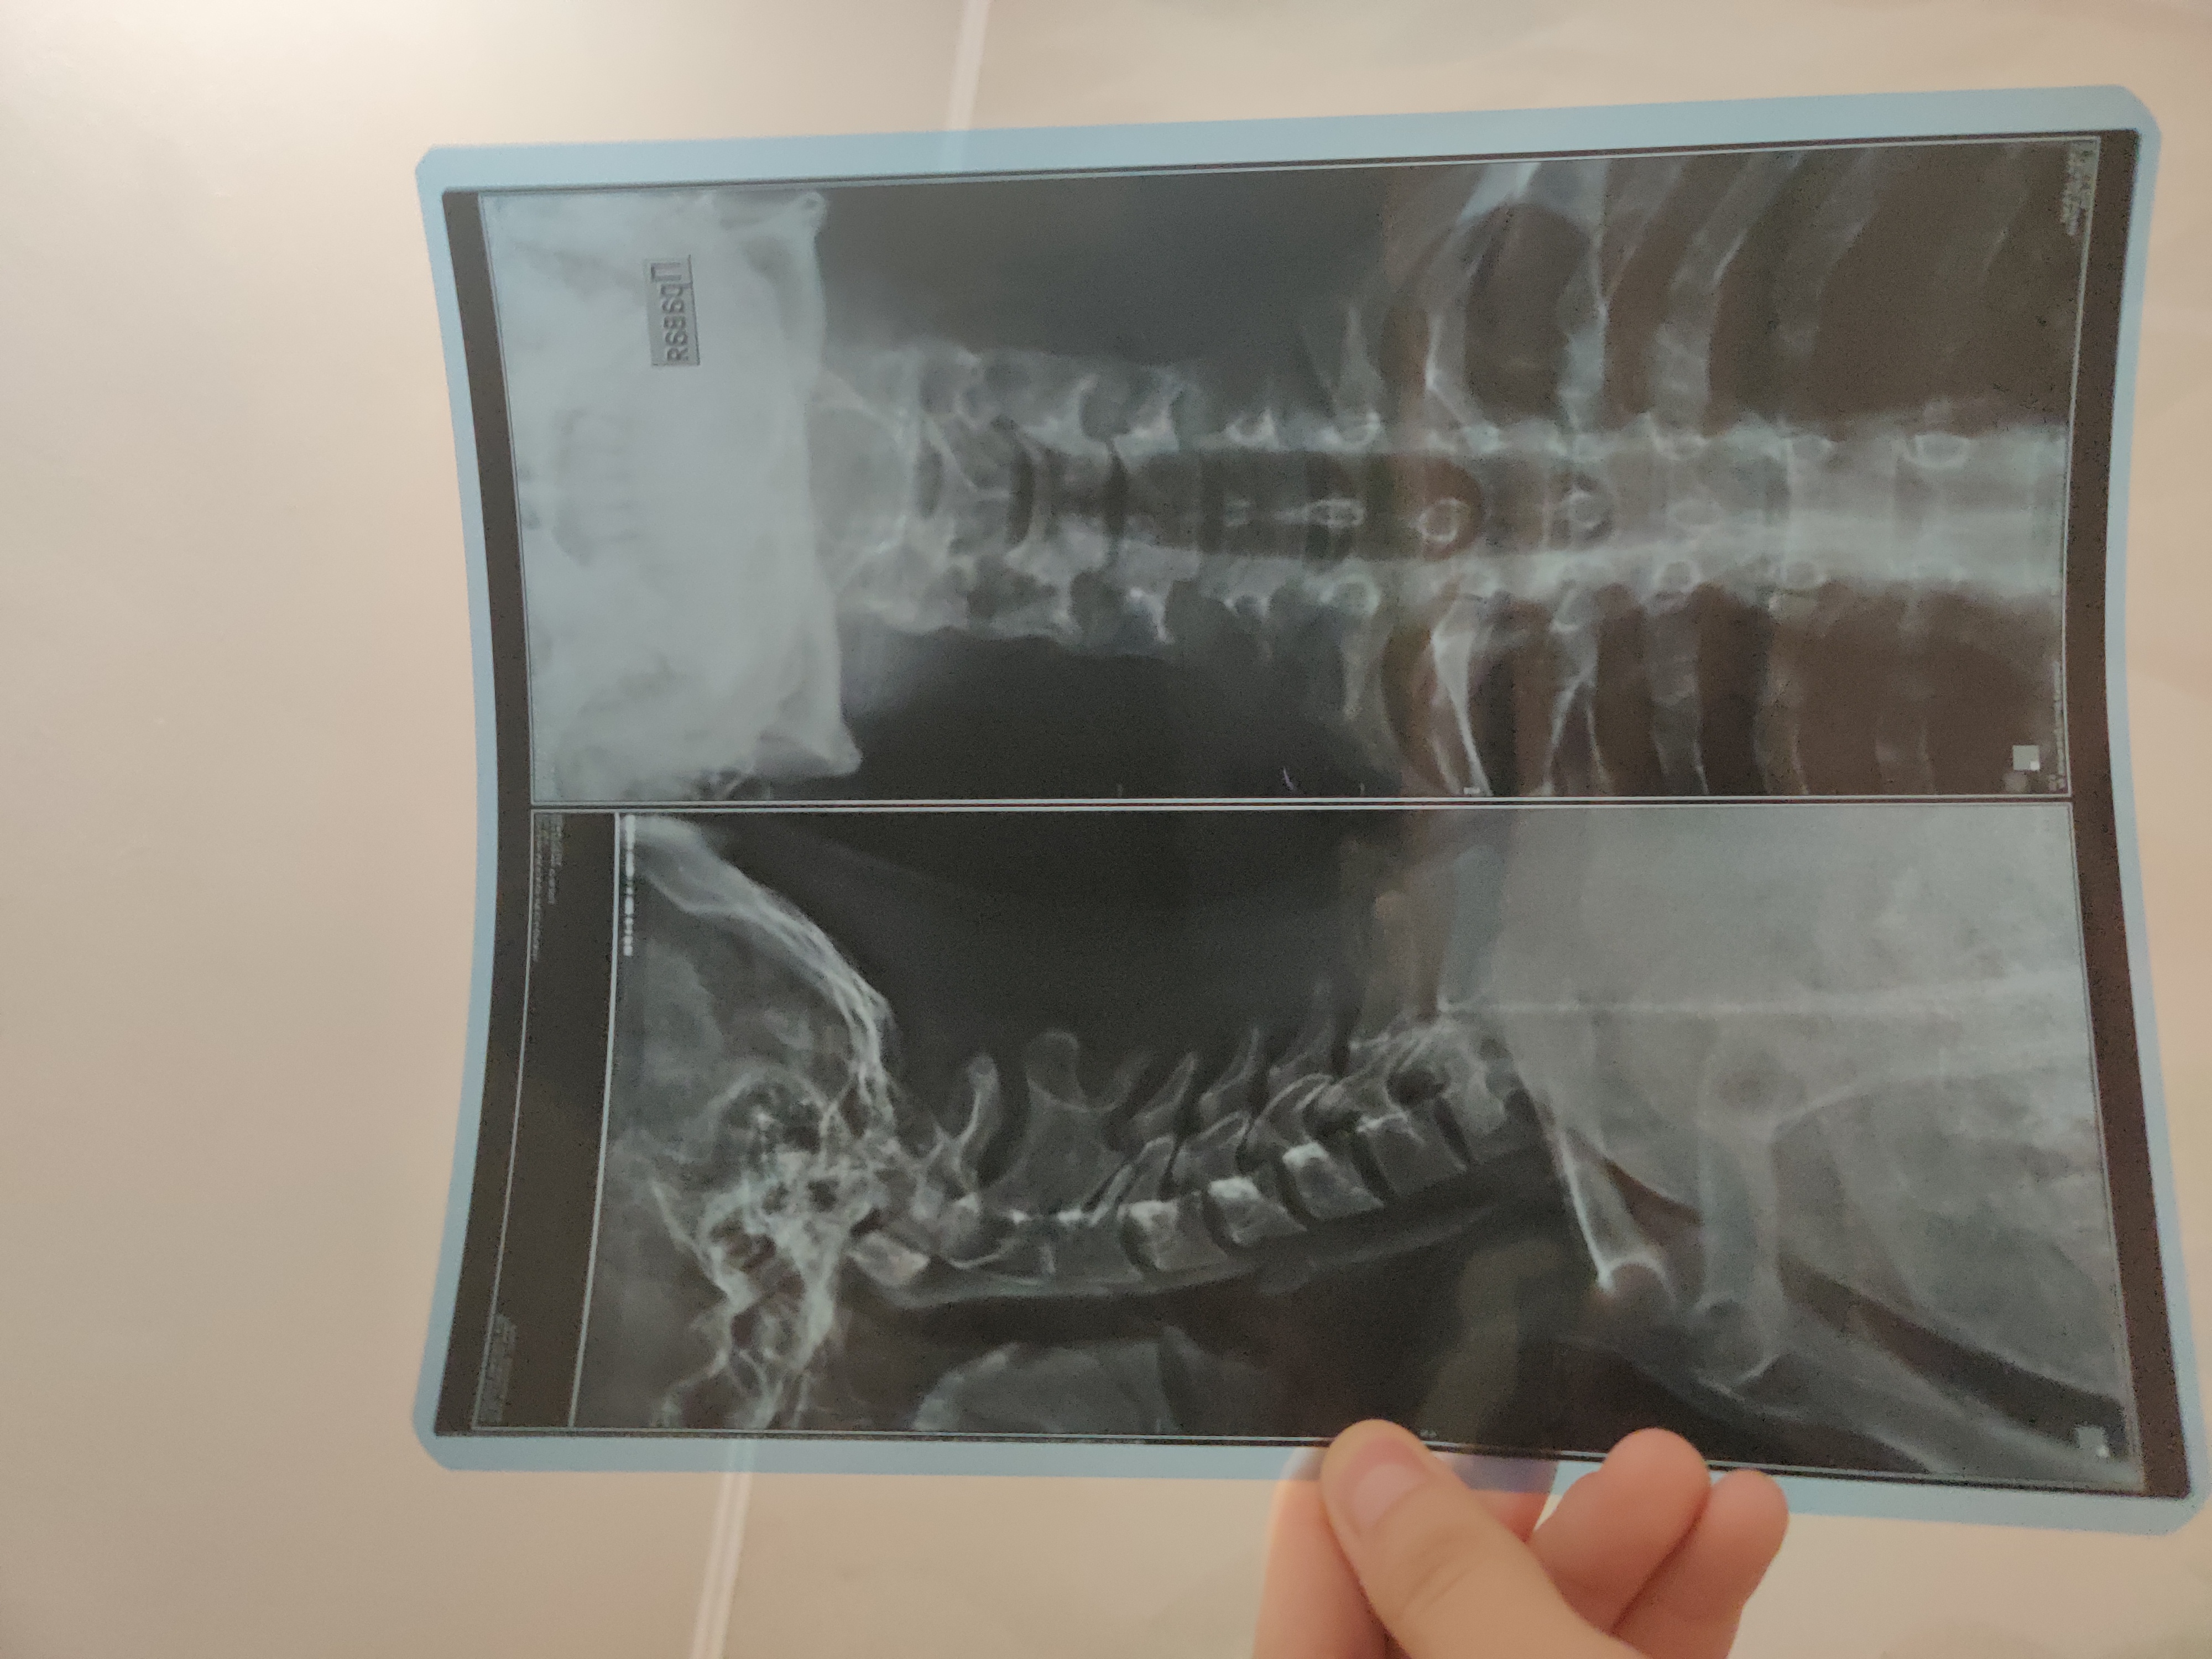

Здравствуйте! В недавнем времени я начал проходить обследование в частной клинике. Сейчас живу в другой области, не по прописке, поэтому проблематично часто ездить и записаться к своему терапевту (завтра буду ехать в родной город и хочу пожаловаться терапевту на боли в шее и просить направление, исходя из рентгена, но не знаю, есть ли шанс получить категорию "B" с заключением на картинке).

Насчет самого обследования, сходил в частную клинику на рентген шейного отдела позвоночника и сейчас получил данное заключение. Подскажите пожалуйста, стоит ли по такому заключению идти к терапевту и жаловаться на боли (боли в шее почти каждый день, иногда очень сильные, после долгой ходьбы) или, судя по этим записям, уже не получится освободиться по шейным заболеваниям?

Травма позвонков C2-C3 была зафиксирована еще в младенчестве. Появился остеохондроз и спондилез.